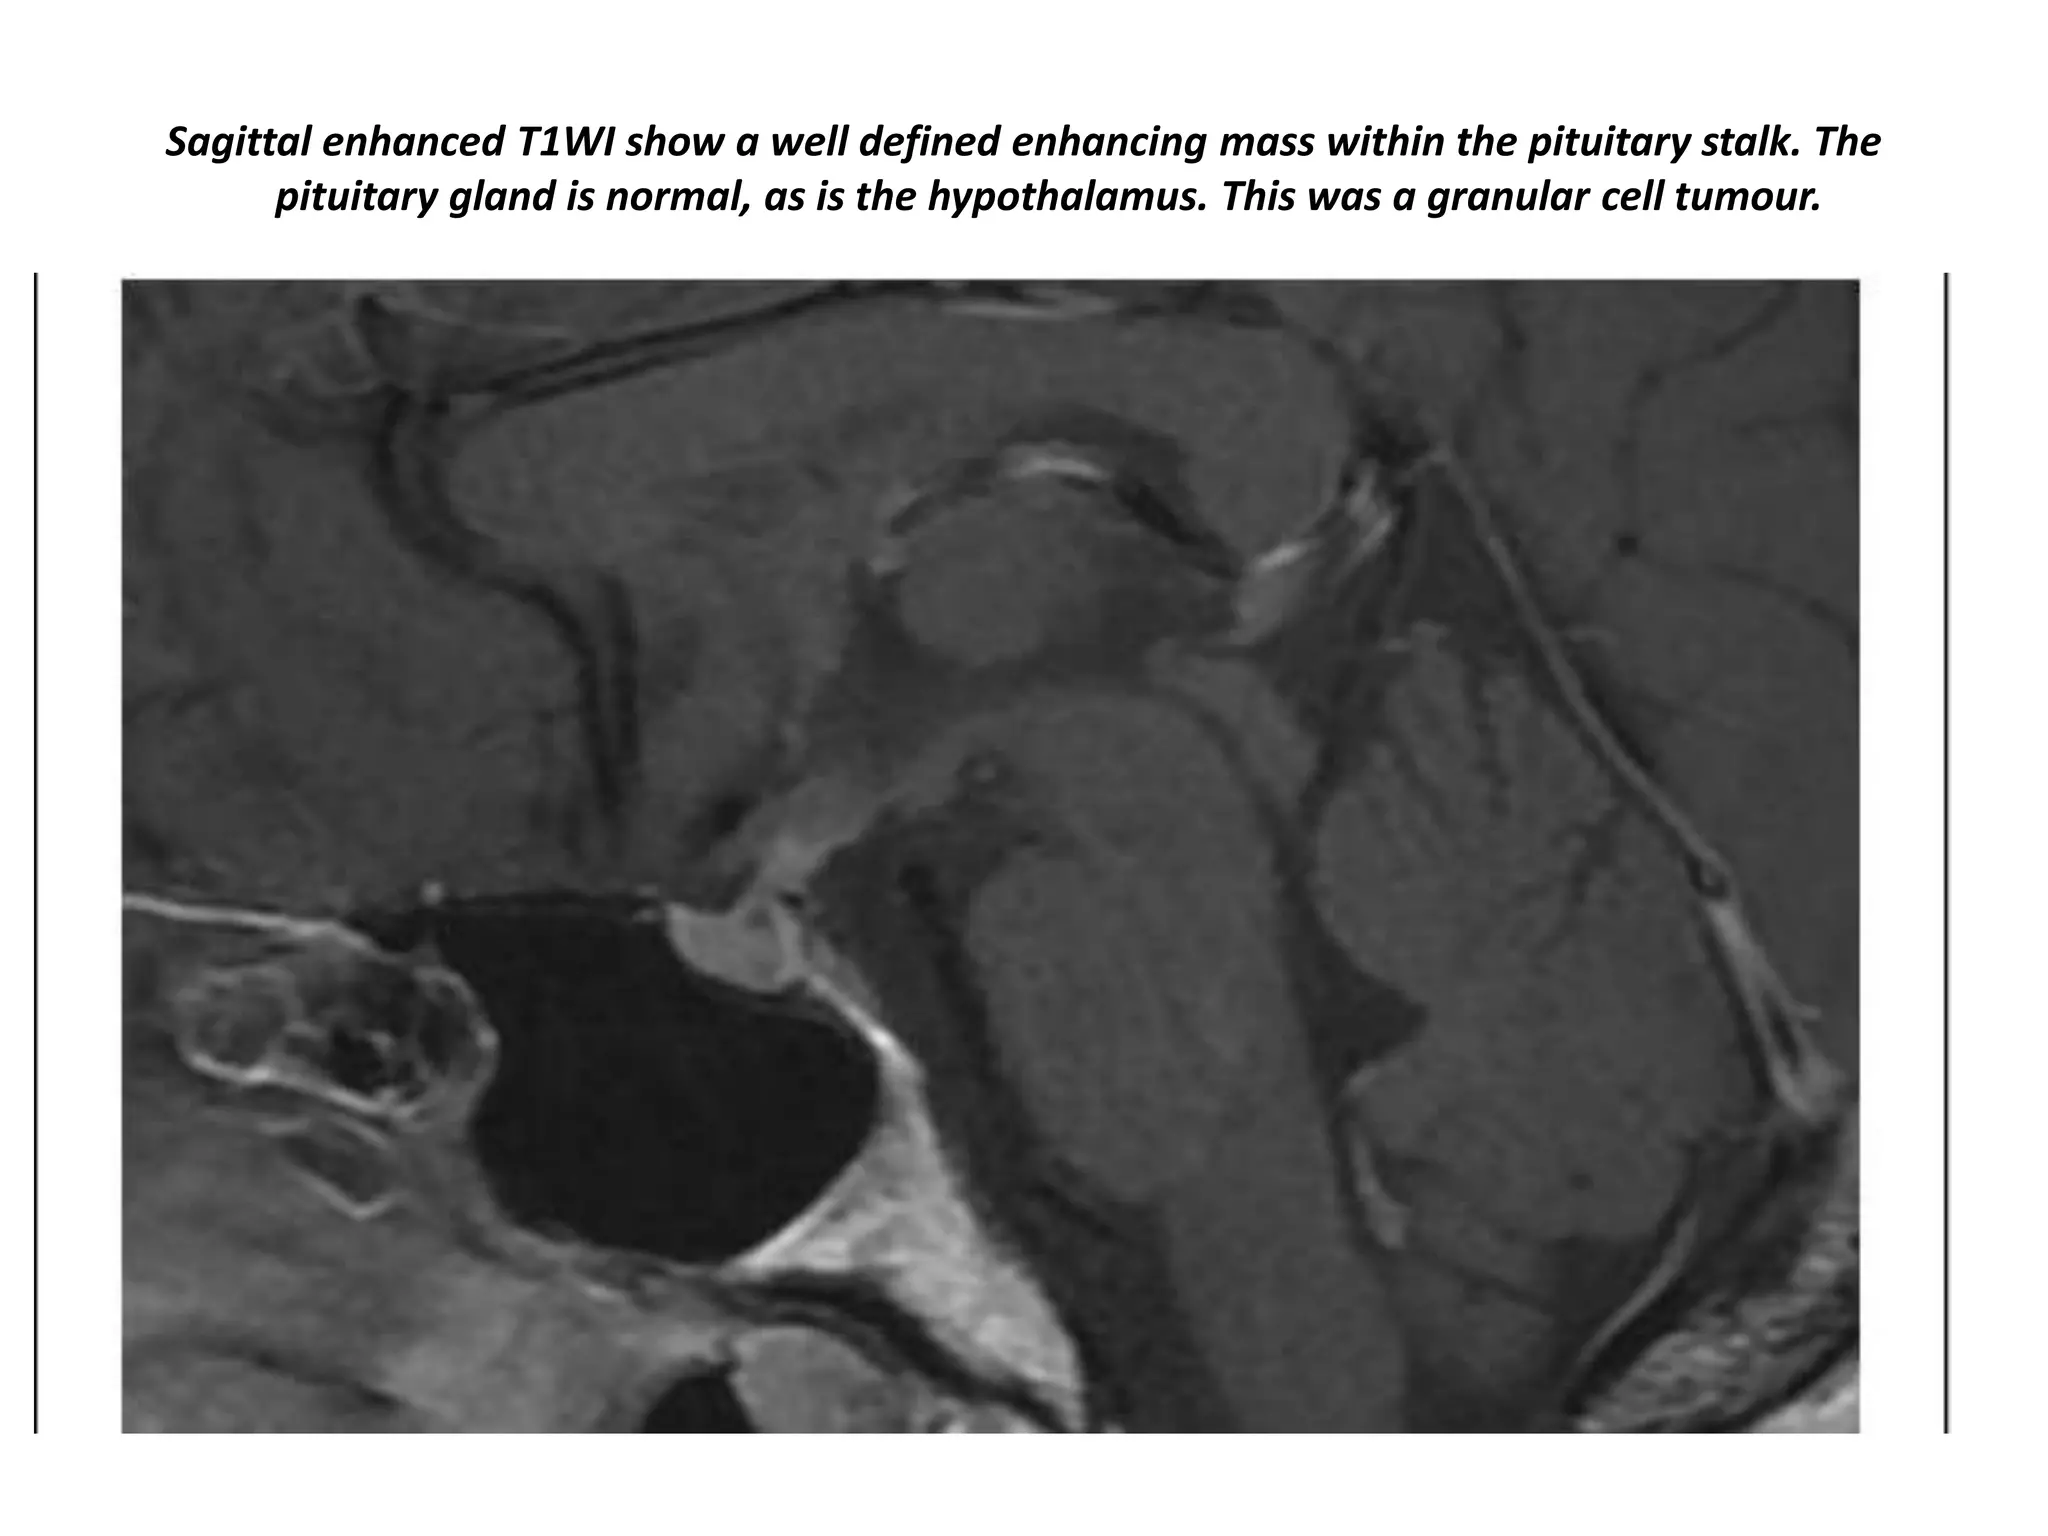

Sagittal enhanced T1WI show a well defined enhancing mass within the pituitary stalk. The

pituitary gland is normal, as is the hypothalamus. This was a granular cell tumour.